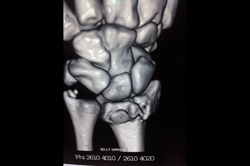

Scaphoid